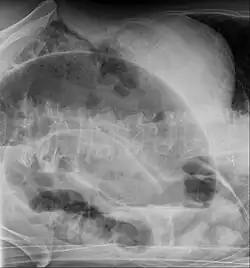

Die Diagnose wird anhand der Klinik und Röntgenaufnahmen des Abdomens (ggf. mit Kontrastmittel), neuerdings auch mittels Ultraschall, gestellt. Die Diagnosefindung insbesondere im Neugeborenenalter kann schwierig sein, da die Klinik lediglich eine Schwellung des Bauches zeigt, und das Röntgenbild unspezifisch sein kann.

Beim Volvulus des Colon sigmoideum findet sich bedingt durch eine massive Überblähung dieses Darmanteils häufig ein so genanntes Kaffeebohnenzeichen (engl. Coffee-bean sign), bei dem eine aufsteigende Schlinge dicht an eine absteigende gelegt ist, so dass sich die Kontur einer übergroßen Kaffeebohne ergibt. Bei bereits stattgehabter Perforation findet sich im Röntgenbild so genannte „freie Luft“.